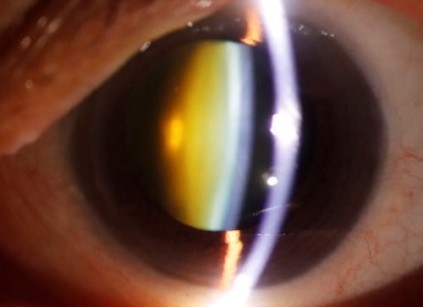

Καταρράκτης

Τι είναι ο καταρράκτης; Ο καταρράκτης είναι η κύρια αιτία αναστρέψιμης μείωσης της όρασης στην Ελλάδα και σε όλο το δυτικό κόσμο. Πρόκειται για την θόλωση του κρυσταλλοειδούς φακού του ματιού. Ο φυσιολογικός φακός του ανθρώπου με την πάροδο των…